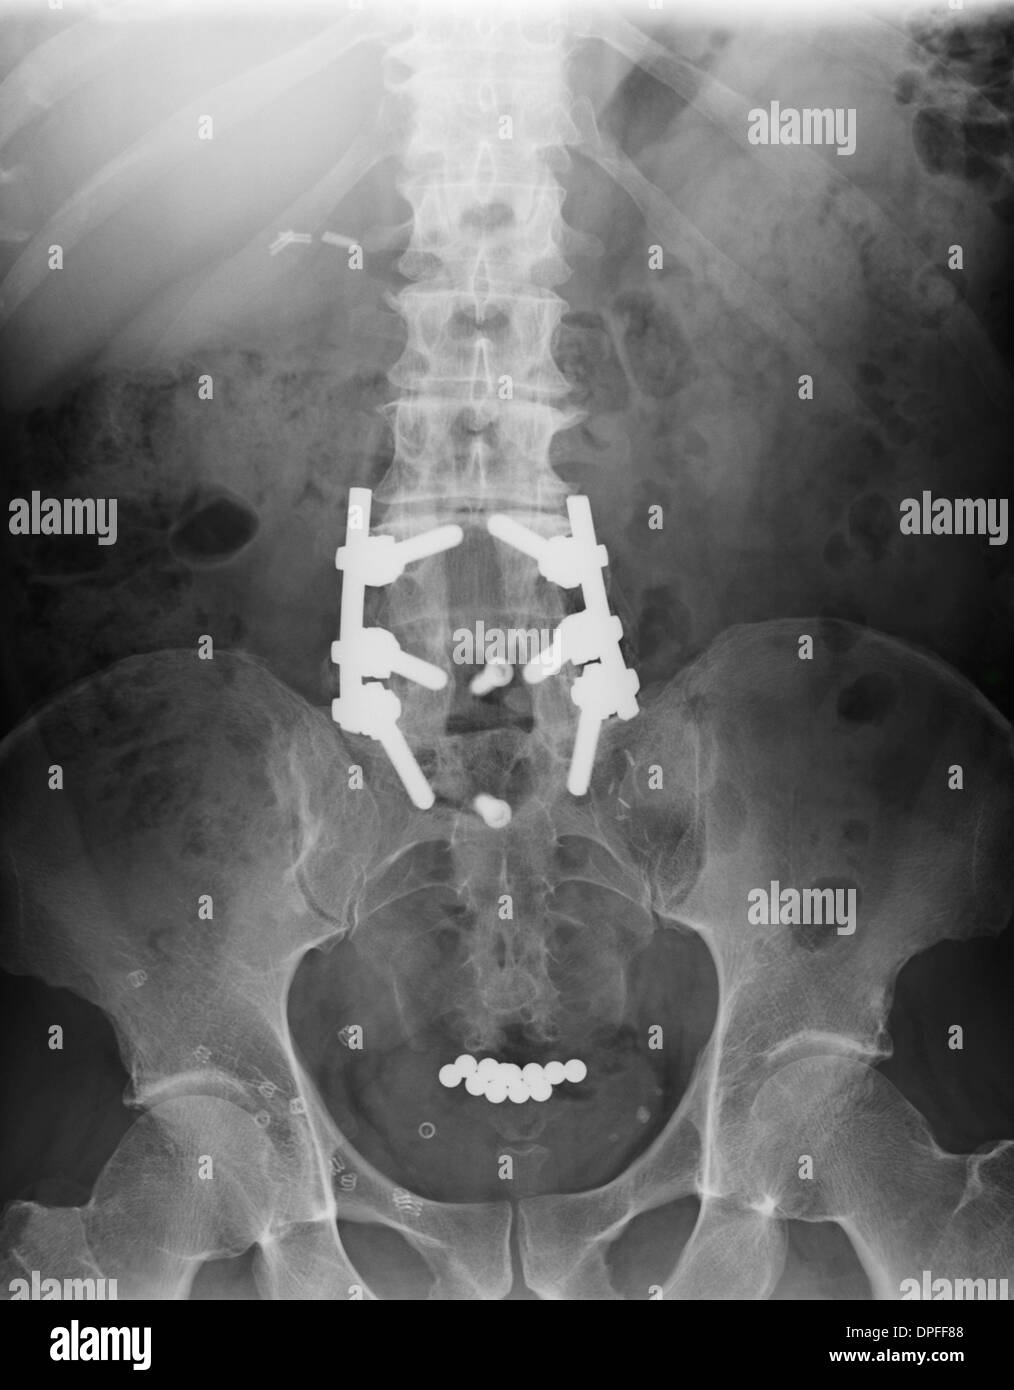

Die Abbildung zeigt einen Zustand nach Spondylodese der zwei untersten Lendenwirbelkörper (LWK4 und LWK5) mit dem ersten Sakralwirbel (SWK1) zwei Jahre nach der Operation. Der Zwischenwirbelraum zwischen dem vierten und dem fünften Lendenwirbelkörper ist bereits knöchern überbrückt (ankylosiert); beim Übergang vom fünften Lendenwirbelkörper zum ersten Sakralwirbel fehlt diese knöcherne Durchbauung. Wenn alle verblockten Wirbelkörper stabil knöchern miteinander verbunden sind, kann das Spondylodesematerial entfernt werden.